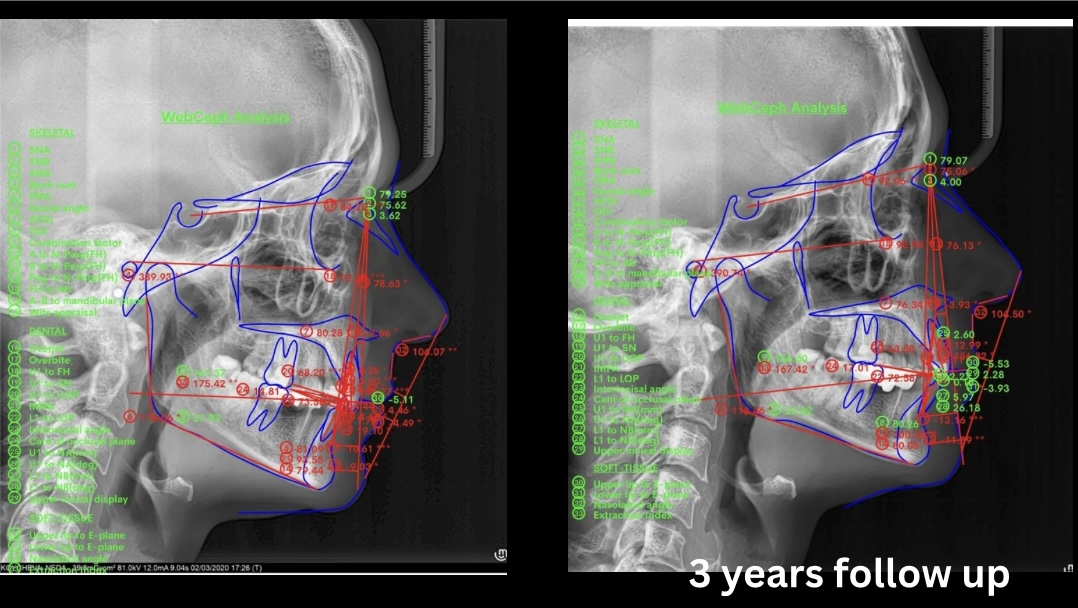

По време на ортодонтския конгрес на GC в София имай ограничено време да представя този интересен клиничен случай, затова направих подробно разглеждане на всички специфики на избора ми за протокол с порцеланови самолигиращи брекети и термоактивни дъги с памет за предвидими резултати.  Вижте в подробности моя протокол за ежедневна работа. Д-р Титева

Орто протокол SLB+ BioEdge дъги- Cl.II, Дълбока оклузия, гингивална усмивка- резюме на клиничен случай

• Course

• 2 Lessons

• 30-day access

Стъпка по стъпка лечение с брекети при Cl.II, дълбока оклузия, гингивална усмивка и симптоматика от ТМС.

Използвани са самолигиращи брекети и Bio Edge термоактивни дъги с памет и контролирана сила, стартирано е директно с квадратна дъга.

Период на лечение- 1г. и 2 м., 7 посещения.

Проследяване на резултата клинично и рентгенографски 3 години след лечението.